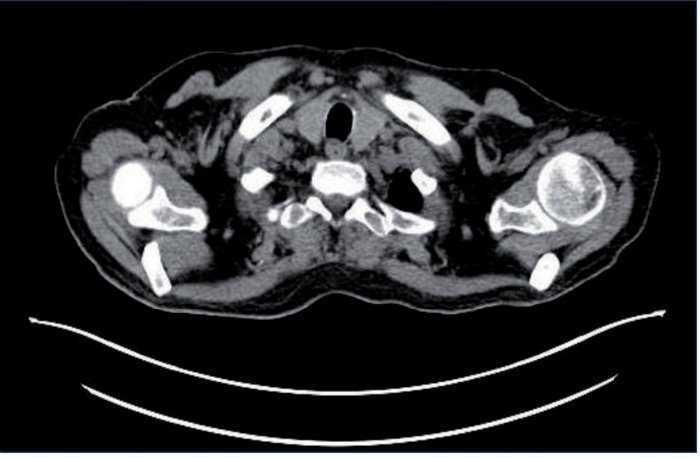

Se detecta PCR-VEB (PCR de virus Epstein-Barr) positiva con 14.000 copias/ml. Se realiza PET-TC (tomografía por emisión de positrones) (fig. 1), a pesar de que el estudio radiológico con TC body no presentó datos significativos. Se objetivan adenopatías hipermetabólicas supradiafragmáticas (supraclavicular izquierda, axilares derechas, mediastínicas paratraqueales bilaterales, precarinal, subcarínica-paraesofágica, hiliar izquierda) e infradiafragmáticas en hilio hepático, a nivel esplénico y óseas, compatibles con malignidad. Estos hallazgos son sugerentes de síndrome linfoproliferativo (SLP) como primera opción diagnóstica.

Figura 1. Adenopatías supradiafragmáticas.